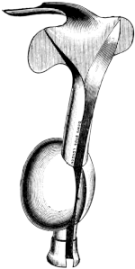

| 37. | Auvard’s Self-retaining Speculum | 136 |

| 255. | Horsford’s Instrument for transfixing the Epiglottis | 478 |